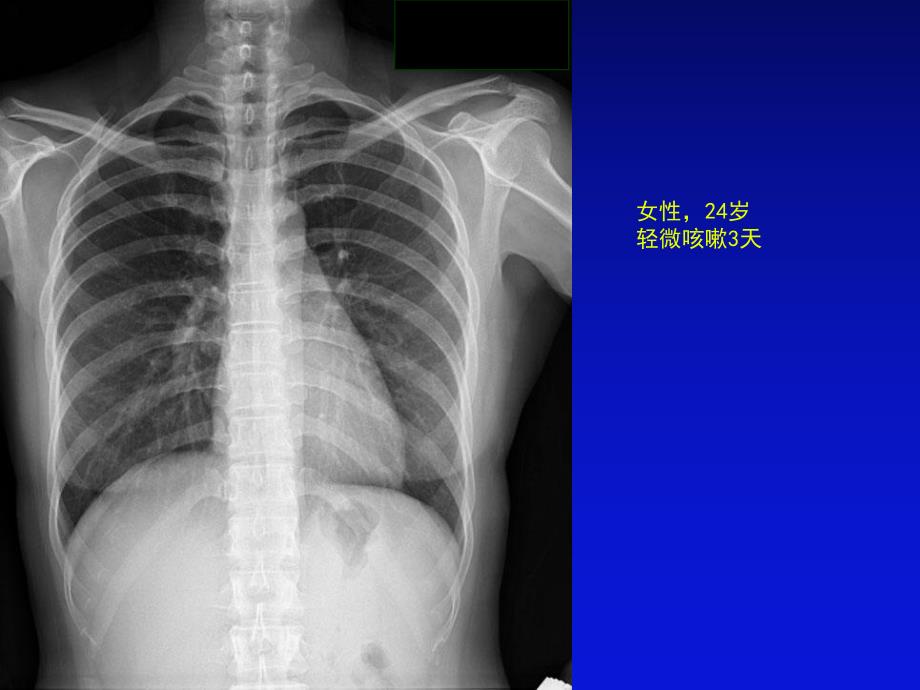

1、女性,24岁轻微咳嗽3天 种类和检查方法种类和检查方法:胸部后前位片胸部后前位片 描述描述:胸廓对称、无骨折和软组织肿胀;胸廓对称、无骨折和软组织肿胀;纵膈居中,无纵膈异常增宽表现;纵膈居中,无纵膈异常增宽表现;心影形态正常,心胸比例小于心影形态正常,心胸比例小于0.50.5;膈肌呈穹窿样,光滑、肋膈角锐利膈肌呈穹窿样,光滑、肋膈角锐利,无异常下移或上抬表现;无异常下移或上抬表现;双侧肺门对称、无异常肺门增大;双侧肺门对称、无异常肺门增大;两肺纹理清晰,无肺内异常密度表现。两肺纹理清晰,无肺内异常密度表现。初步诊断初步诊断:正常胸片正常胸片男性,12岁咳嗽、发热 种类和检查方法种类和检查方法: